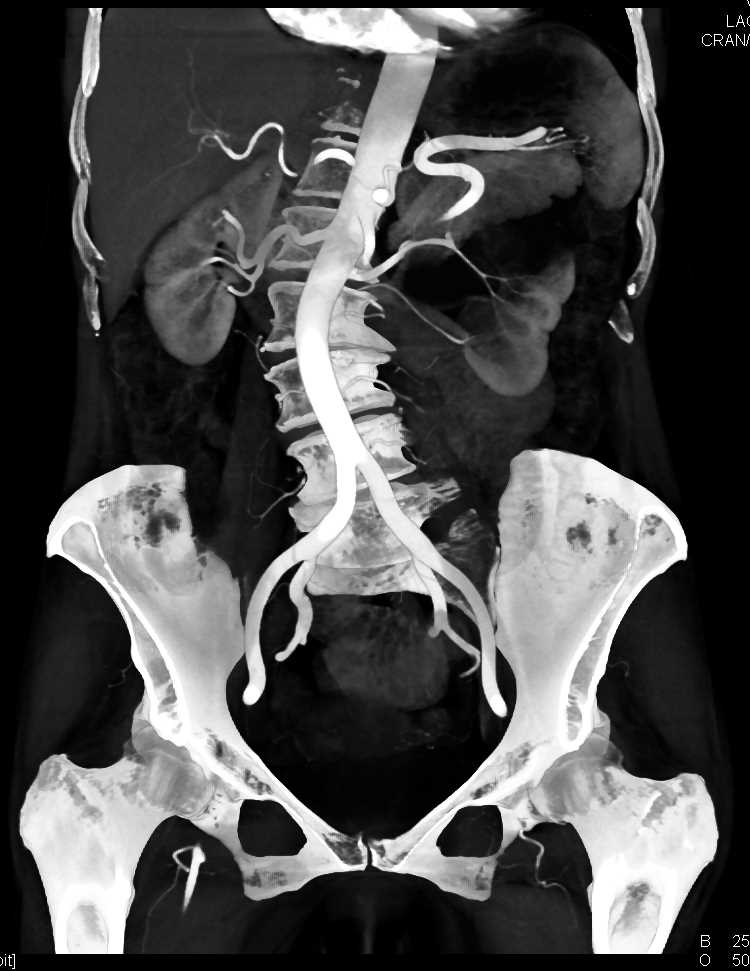

Parapelvic Cysts Left Kidney